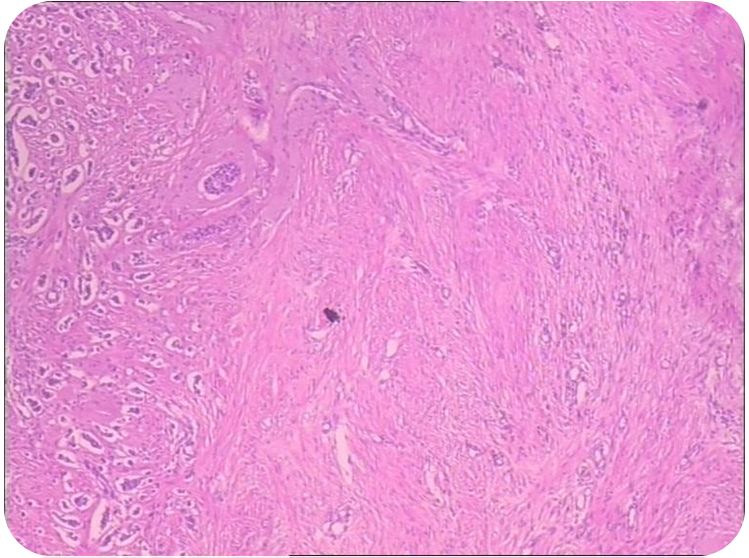

病理:左乳浸润性导管癌Ⅱ级(肿瘤大小2.5*2.3cm)。

免疫组化:ER(+40%强阳),PR(+30%中阳),HER-2(2+),FISH(-),KI-67(阳性细胞数约40%)。未见脉管内癌栓。腋窝前哨淋巴结活检:前哨1a,1b,前哨2,前哨3均未见癌转移。

进一步行fISH检查示:HER-2无扩增。(如右图)

本例是一位确诊时年龄53岁、绝经前、已婚已育的乳腺癌患者,术后诊断:左乳癌(pT2N2bM0,IIIa期)。术后左乳浸润性癌免疫组化提示: ER 强阳40% ,PR 中阳30%,c-erbB-2(BC) 2+,FISH(-),Ki-67 40%+,CD34,D2-40未见脉管内癌栓。对这样一个中期LuminalB型乳腺癌患者,术后辅助治疗实际涉及三个方面:术后辅助化疗、放疗、术后内分泌治疗。